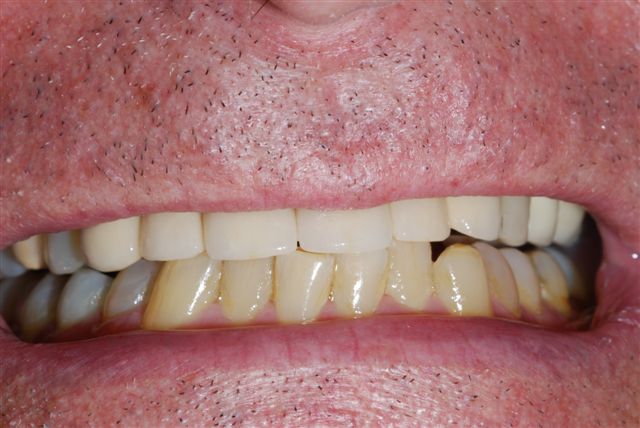

Before

After

Andrew wanted a full, young, and more esthetic smile. Dr. Sreter was able to achieve harmony of esthetics and function utilizing ceramic crowns.